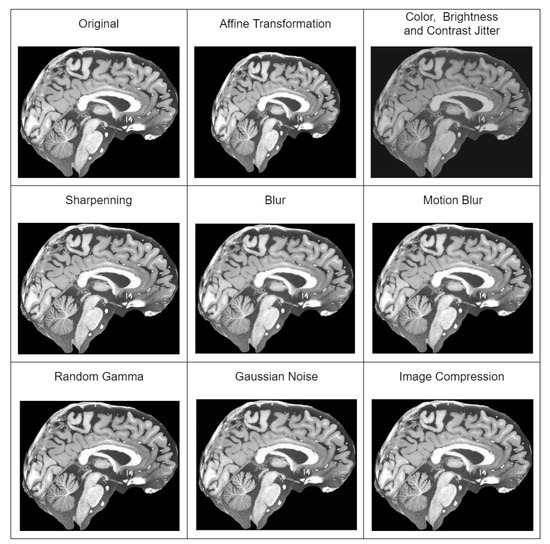

In our case, a model used for sMRI super-resolution must be practical and capable of dealing with a wider distribution of input images than the training set. Hence, the extensive application of random augmentations (degradations) during training. Original pipeline includes blur, resize, Gaussian noise, Poisson noise, speckle noise, and jpeg compression noise transformations applied in random sequence multiple times. We extended the original pipeline with the additional random augmentations of brightness and contrast jitter, sharpening, gamma, cutout, and random rotation transformations. All used augmentations are depicted in Figure 1.

• Additionally using augmentation techniques—affine transformation, color, brightness and contrast jitter, sharpening, blur and motion blur, Gaussian noise, gamma, and image compression transformations. All of the augmentation techniques used are depicted in Figure 2.